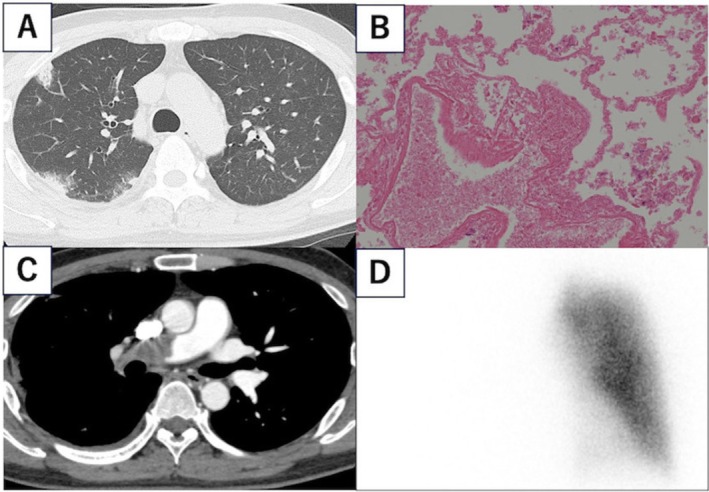

39岁男性,发热、呼吸困难1周。影像学提示右肺浸润性细菌性肺炎。然而,尽管使用抗生素,症状仍然存在。支气管镜检查显示凝固性坏死,增强计算机断层扫描发现右肺动脉有大血栓,诊断为肺梗死。患者直接口服抗凝剂治疗。两年后,在右肺上叶观察到新的结节性病变伴空洞。支气管镜检查显示鸟分枝杆菌感染。我们假设非结核性分枝杆菌(NTM)肺病可能并发慢性肺栓塞。

A 39-year-old man presented with fever and dyspnoea for 1 week. Imaging suggested bacterial pneumonia with infiltrates in the right lung. However, the symptoms persisted despite antibiotics. Bronchoscopy revealed coagulation necrosis, and enhanced computed tomography identified a large thrombus in the right pulmonary artery, leading to a diagnosis of pulmonary infarction. The patient was treated with direct oral anticoagulants. Two years later, new nodular lesions with cavities were observed in the upper lobe of the right lung. Bronchoscopy revealed a Mycobacterium avium infection. We hypothesise that nontuberculous mycobacterial (NTM) pulmonary disease may complicate chronic pulmonary embolism.